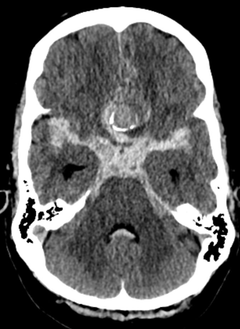

Tutkijat tarkastelivat aivovaltimopullistumien eli aneurysmien hoidon laatua. Tutkimuksessa seurattiin 169:ää potilasta, joita hoidettiin HUSissa joko mikrokirurgisesti (29 prosenttia potilaista) tai suonensisäisesti (71 prosenttia) joulukuun 2022 ja elokuun 2024 välisenä aikana.

Vaikka potilaiden kliininen vointi oli erinomainen, tutkimuksessa tehdyt herkät diffuusiomagneettikuvaukset (DWI) paljastivat uusia, pieniä iskeemisiä eli hapenpuutteesta johtuvia muutoksia 63 prosentilla potilaista. Valtaosa näistä oli oireettomia, mutta ne olivat yhteydessä kohonneeseen riskiin saada ohimeneviä neurologisia oireita. Tulos osoittaa, että perinteiset toimintakyvyn mittarit eivät tavoita kaikkia hoidon vaikutuksia aivoihin.